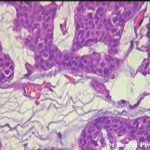

There are solid and cystic aggregations of neoplastic cells within the dermis, often with extension to the subcutis, embedded in large pools of mucin. Mucinous areas are typically separated by fibrous septae.